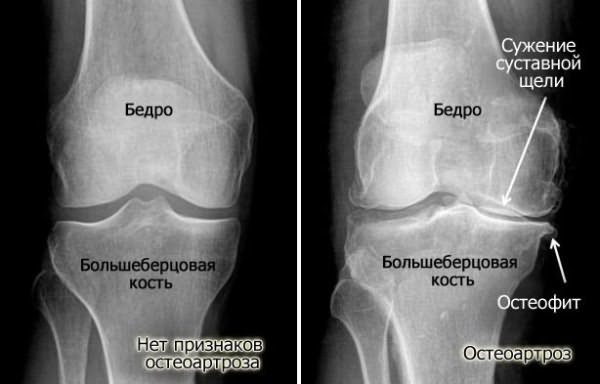

Обнаруживают сужение суставной щели. В начальных стадиях заболевания обычно поражается внутренний или наружный отделы сустава, и сужение суставной щели наблюдается только с одной стороны. С течением времени процесс распространяется на весь сустав. Подхрящевая костная пластинка уплотняется.По краям суставной поверхности обнаруживаются костные разрастания – остеофиты.На УЗИ выявляется истончение гиалинового хряща, хондромаляция, дегенеративно-дистрофические изменения в менисках и связочном аппарате, при синовиите - жидкость в заворотах синовиальной оболочки. При артроскопии определяются зоны эрозии на суставных поверхностях бедреной кости, разволокненные мениски, гипертрофия ворсин синовиальной оболочки.